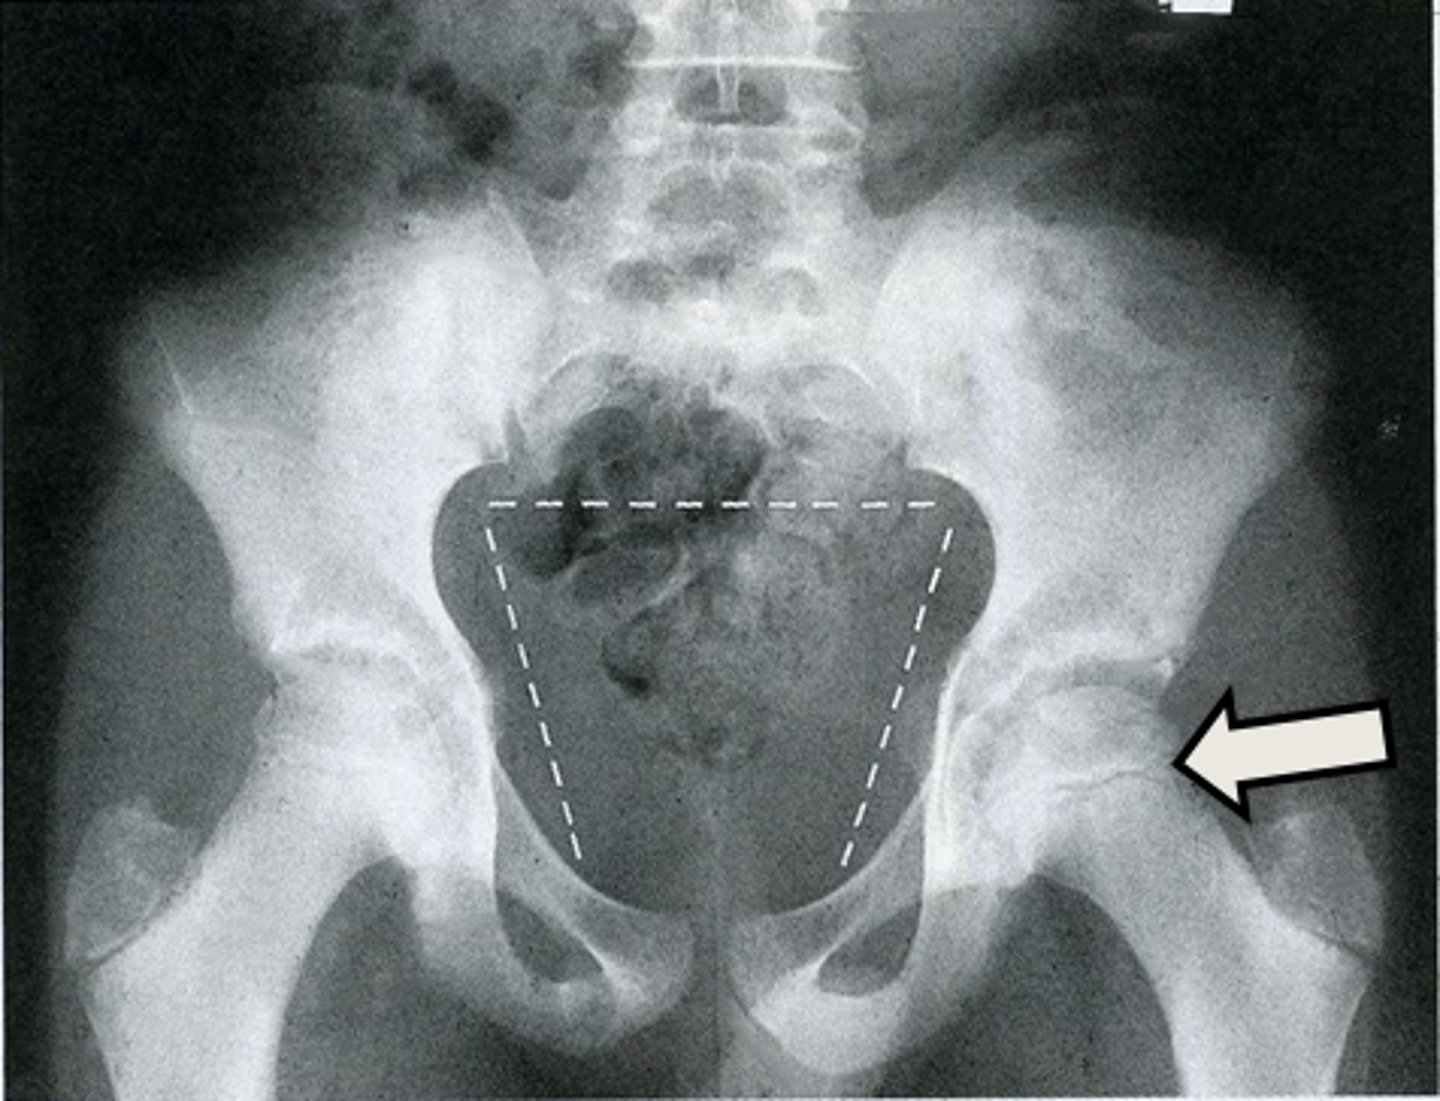

AP pelvis

What is the image?

2

Acetabulum

What is indicated in the image?

3

Body of L4

4

Epiphysial plate

5

Femoral head

6

Hip joint

7

Ilium

8

Ischial spine

9

Ischial tuberosity

10

Nonfused greater trochanter

11

Obturator foramen

12

Pubic symphysis

13

Sacroiliac joint

14

Sacrum

15